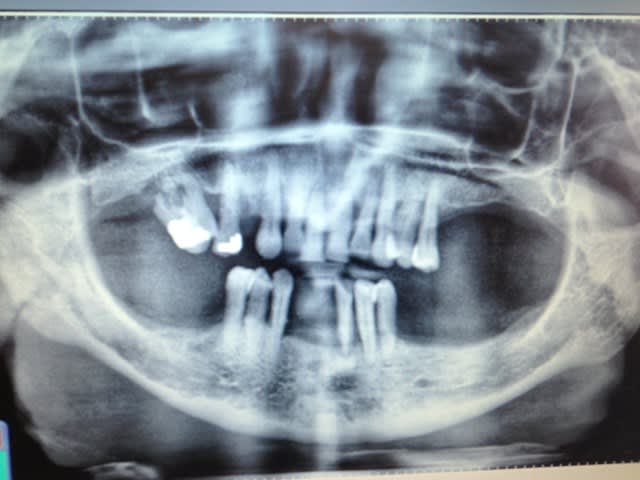

Bonjour, étant jeune praticien et par conséquent n'ayant pas beaucoup de recul sur les plan de traitement je poste se petit sujet pour solliciter des conseils.

Voici mon plan de traitement:

mandibule: extraction et prothèse complète

maxillaire: chirurgie d'assainissement parodontale + bridge de contention de 13 à 23 (voir 25) + chassis.

Ma question est surtout pour le maxillaire et sur la durabilité du bridge.

Pour le haut il faudra voir si il reste suffisamment de dents stables pour faire une partie fixe après l'assainissement paro.

Tu peux laisser entendre que oui, mais avec de grosses réserves, en effet, tu ne vas pas garder 2 dents au milieu d'un stellite...

J'ai effectivement émis des réserves sur le haut en disant que je réévaluerai le niveau osseux au moment de la chirurgie parodontale.

Cependant je me vois mal faire la chirurgie parodontale, attendre la cicatrisation pour réévaluer la mobilité puis lui annoncer que finalement il faut tout extraire et faire des prothèses complètes!